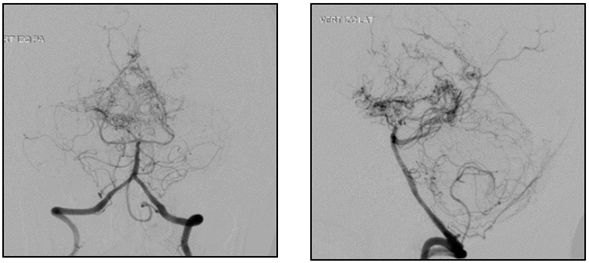

Paciente femenina de 45 años de edad de etnia mestiza sin antecedentes patológicos, quien ingresa al servicio de urgencias de un hospital de cuarto nivel de la ciudad de Cartagena (Bolívar) el día 1° de julio de 2019 con cuadro clínico de una semana de evolución consistente en cefalea holocraneana, de moderada intensidad, con posterior aparición de un episodio convulsivo tonicoclónico generalizado, con relajación de esfínteres, sin especificarse la duración de la crisis. Al ingreso al servicio de urgencias tensión arterial de 140/90 y restantes signos vitales normales sin déficit neurológico focal. Se realizó una tomografía de cráneo simple evidenciando foco hemorrágico intraparenquimatoso de localización gangliobasal derecho, leve enfermedad multifocal isquémica de pequeños vasos, foco malásico occipital derecho y evento isquémico antiguo frontal izquierdo adyacente al ventrículo lateral izquierdo (Figura 1). En los paraclínicos iniciales no se encontró alteración en la analítica sanguínea con reporte de hemoleucograma y recuento de plaquetas normales, azoados, ionograma y tiempos de coagulación dentro de límites de normalidad. Se realizó panangiografía cerebral encontrando como hallazgos: adelgazamiento de arterias carótidas internas y de cerebrales posteriores (observable esto último en el 50% de los casos) con presencia de neovascularización anormal a nivel de núcleos de la base, compatible con enfermedad de Moyamoya (Figura 2). Con estos resultados se evaluó en junta médica de neurocirugía la conducta a seguir, considerando que se puede beneficiar de manejo endovascular; sin embargo, ante el alto riesgo de recurrencia del sangrado, se postergó la realización del mismo al menos cuatro semanas.

La enfermedad de Moyamoya es una enfermedad crónica que se caracterizada por estenosis progresiva bilateral de la porción terminal de la arteria carótida interna y sus ramas proximales con la consiguiente neoformación de una red arterial colateral anormal de las arterias que forman el polígono de Willis de etiología hasta ahora desconocida 1-3. El término proviene de la apariencia similar al "humo de cigarro en el aire" (Moyamoya en japonés) de las arterias colaterales observadas por angiografía que se forman de forma progresiva durante la evolución de la enfermedad 2.

Para el diagnóstico se utilizan diversas pruebas que evalúan la vasculatura cerebral como la angiotomografía y la angiorresonancia con buenos resultados. Sin embargo, la panangiografía cerebral (también conocida como angiografía por sustracción digital) es el "gold standard" en el diagnóstico definitivo de la enfermedad de Moyamoya al observarse el aspecto arteriográfico característico. Ésta detecta la estenosis de la porción terminal de la arteria carótida interna y sus ramas proximales así como también la formación de la red de colaterales 4. La panangiografía cerebral en nuestro caso fue solicitada como parte del estudio de hemorragia intracraneal en un paciente joven y evidenció adelgazamiento progresivo de ambas arterias carótidas internas con presencia de neovascularización y desaparición bilateral de arterias cerebrales media y anterior.